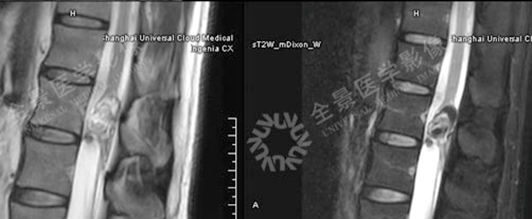

MR显示病灶与脊髓的关系,压脂序列呈低信号; CT可显示病灶内钙化,可见少许脂肪密度;

骨关节

案例 :骨巨细胞瘤

T2WI不均匀等信号,

PET/CT显示:T3骨质破坏并周围软组织肿块形成,FDG明显摄取增高。

增强扫描明显强化